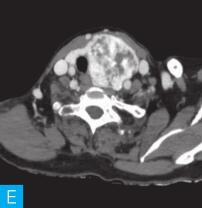

甲状腺CT检查:CT检查设备为256层iCT,病人采取仰卧位,扫描范围自外耳道平面至下颌角以下,常规扫描层厚为0.9mm、层间隔0.9mm,电压120kV,管电流280mA,矩阵512×512;经右肘静脉团注法增强扫描,碘海醇80ml,流速4ml/s,动脉期25秒扫描,静脉期60秒扫描。见图1。

图1 甲状腺CT

A、B.甲状腺CT横断面平扫;C~H.甲状腺CT横断面增强

答案A 解析:甲状腺左叶病变边界清楚,形态较规则,密度不均匀,部分为实性改变,部分为囊性灶,其内可见斑点状粗大钙化灶,气管及食管向右推移,左侧颈总动脉向左后推移,胸锁乳突肌向左前推移。根据表现病变不是单纯囊性病变。

答案C 解析:该病灶病史时间长,无发热及疼痛;病变位于一侧甲状腺,边界清楚;甲状腺血流及静态显像示:甲状腺左叶较大“凉”结节。因此不考虑恶性肿瘤及感染性病变。病变强化特点为结节状改变,呈现肿块样,故考虑肿瘤样病变。

CT平扫可见甲状腺左叶圆形以低密度为主病灶,大小为8.0cm×6.5cm,边界清晰,边缘尚光整,其内密度不均匀,低密度区CT值18HU,部分密度稍高,并可见斑点状粗大钙化影;CT增强后,甲状腺左叶病变呈不均匀渐进性强化,结节状改变,动脉期强化区CT值99HU,静脉期CT值85HU,且强化范围增大,提示该病变的血供较为丰富,应该考虑肿瘤样病变,结节性甲状腺肿可能性大。

本病例CT扫描发现起源于甲状腺较为容易,但要观察病变是囊性、实质性或囊实性及其供血,CT增强扫描十分必要,易于显示囊实性病变及其供血情况,其结节状改变更加显著,有助于判定病灶的血液供应情况。本病例基本征象为类圆形、边缘清晰、内粗大钙化、结节状强化之肿块。

该例病变位于甲状腺左叶,左叶不对称性增大,其内多发散在不规则强化结节影,斑点状粗大钙化,钙化周围可见星状伪影,提示钙化为长期慢性形成,而且钙化比较致密。肿块虽然很大,但与邻近气管、食管及血管等无明显侵犯或浸润征象。病变内部可见多发囊变区,增强检查实性部分呈明显均匀强化,包膜完整。双侧锁骨上区未见肿大淋巴结。提示病变为良性。病变多发,伴囊变、钙化,临床为中老年女性病人,颈前无痛性肿物。结节性甲状腺肿诊断明确。结节性甲状腺肿常常较大,术前影像学的评估包括:①病变的范围,累及胸骨下的范围决定手术治疗的方式,手术是否需要打开胸骨;②病变与气管的关系,是否具有气管软化,如果存在气管软化,要提醒临床医生手术过程中以及术后出现呼吸困难;③注意是否合并甲状腺癌,尤其是乳头状癌。要仔细寻找包膜是否完整,内部有无微小的乳头,以及邻近Ⅵ区或Ⅳ区是否伴有淋巴结转移。